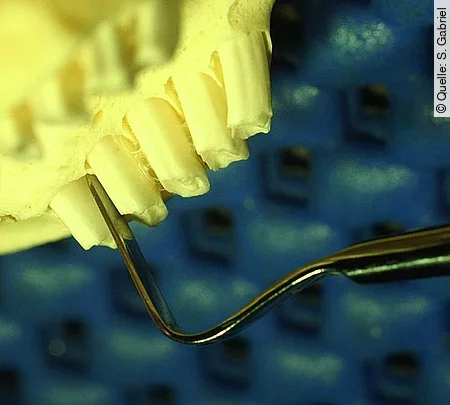

Häufig wird angefragt, ob man einen „störenden“ Backenzahn, z. B. wegen sublingualer Spitzenbildung, nicht einfach ziehen kann. Dazu ist zu bemerken, dass sich ein wurzelgesunder Molar nicht aus der Zahnreihe entfernen lässt, ohne die Nachbarzähne zu schädigen. Das gelingt höchstens bei den endständigen Molaren. Abb. [5] zeigt die bilophodonte Innenstruktur der Molaren. Dies bedeutet, dass ein zusammengesetzter elodonter Zahn aus 2 nebeneinander angeordneten und verbundenen Zahnkörpern besteht, von denen jeder ein eigenes Pulpenorgan besitzt.

Orale Molarenextraktion

In den Abb. [8] und Abb. [9] wird der Einsatz des Luxators am Oberkiefer M2 demonstriert. Der passende Luxator wird an allen Seitenflächen in den Parodontalspalt eingeführt und mit wiegenden Bewegungen in die Tiefe der Alveole gedrückt. Das Instrument wirkt dabei als Keil, der den Zahn nach lateral hebelt. Die scharfe Schneide zertrennt parodontale Fasern. Nach möglichst tiefer Lösung des Parodonts wird der Zahn durch interdentales Hebeln und vorsichtiges Rotieren um seine Längsachse weiter gelockert, bis er in Richtung seiner Längsachse herausgezogen werden kann. Im Unterkiefer ist diese Manipulation wegen der steileren Zahnstellung deutlich schwieriger. In der Enge der Maulhöhle muss der Molar manchmal während der Extraktion vorsichtig geteilt werden, damit man mit der Fasszange nachfassen und tiefer ansetzen kann.